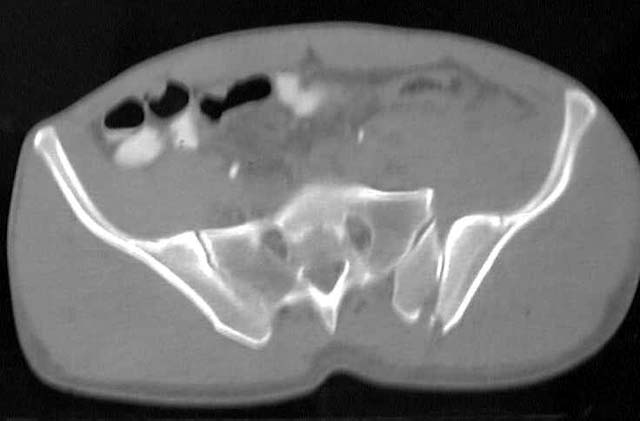

Preop Inlet

Preop Outlet

Preop CT